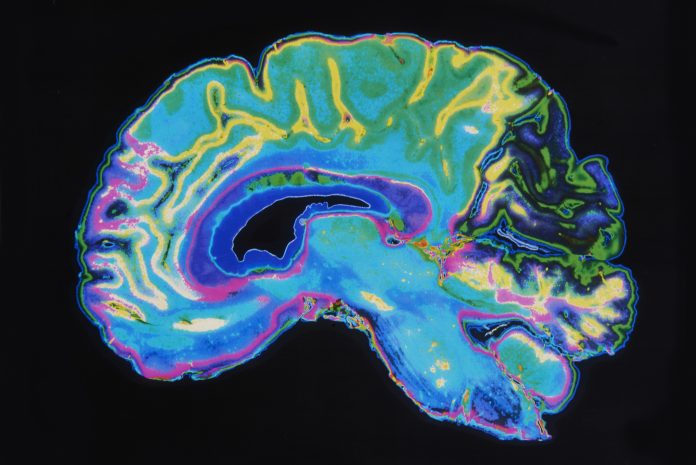

Lecanemab has proven to be the first drug with the ability to slow the destruction of the brain by Alzheimer’s disease.

According to researchers, the drug known as Lecanemab only has a small effect on slowing brain deterioration; however, even this shows promise.

Amyloid is a protein that clumps together in the spaces between neurons in the brain and forms distinctive plaques that are one of the hallmarks of Alzheimer’s. Lecanemab is an antibody that has been engineered to tell the immune system to clear amyloid from the brain.

The disease continued to rob people of their brain power, but that decline was slowed by around a quarter over the course of the 18 months of treatment. This shows no cure but a strong potential for future innovations in Alzheimer’s treatment and care.